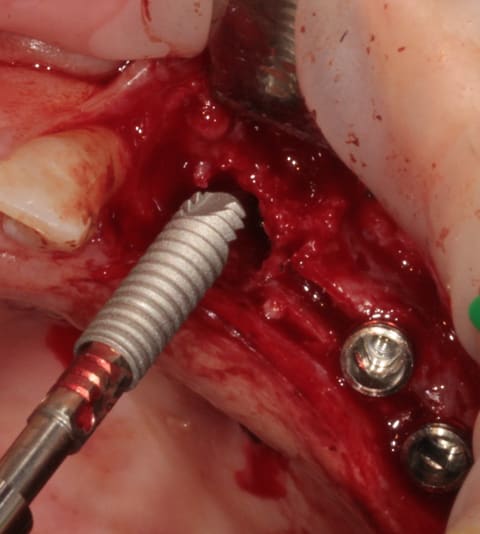

mise en place du conique lisse

L'outil de CLIO

contrôle, axe et profondeur